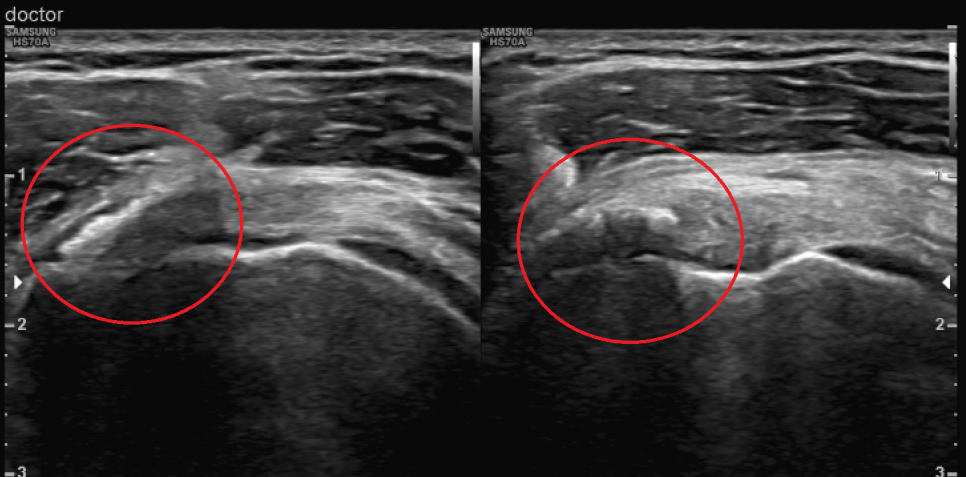

초음파 검사 후 발견된 돌덩이

엑스레이와 초음파 검사상 환자의 양 어깨 회전근개(극상근, 견갑하근)에 석회 덩어리가 관찰되어 어깨의 움직임에 많은 제한이 있는 상태에서 관찰되었습니다. 이러한 것들을 석회성 근염이라고 하며, 유착성 피막염이라고 진단을 받게 되었습니다.